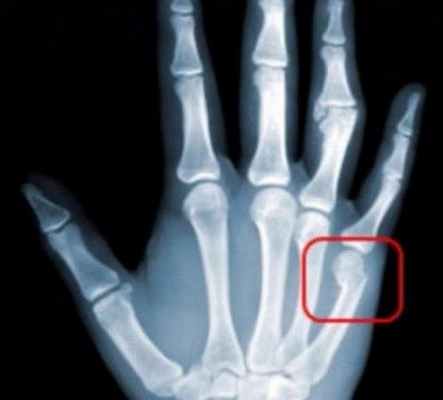

Переломы пястных костей – самый распространенный вид травмы. Его разновидности:

- Перелом I пястной кости происходит при сильном ударе согнутым большим пальцем по твердому предмету.

- Внутрисуставный или внесуставный перелом основания первой пястной кости. Перелом Беннета характеризуется смещением травмированной кости к лучевой кости, при этом треугольный фрагмент не смещается, поскольку его удерживают связки. Перелом Роланда – вывих пястного костного фрагмента к лучевой кости с одновременным разломом первой пястной кости на несколько отломков.

Перелом пястных костей

Перелом пястных костей. Среди наиболее часто встречаемых переломов пястных костей встречаются перелом основания первого пальца, это перелом Беннета и перелом Роланда. Перелом Беннета — характеризуется наличием продольного перелома ладонно-ульнарного края основания I пальца. Как правило, при данном переломе отломок треугольной формы, незначительно смещается, так как удерживается связками.

Первая пястная кость смещается в проксимальном направлении. Перелом Роланда — это многооскольчатый перелом основания I пястной кости. данный вид перелома. При осмотре выявляется деформация и отёк в области 1-го пястно-запястного сустава. Осевая нагрузка на 1-й палец болезненна. При переломе I пястной кости большой палец приведён и несколько согнут.